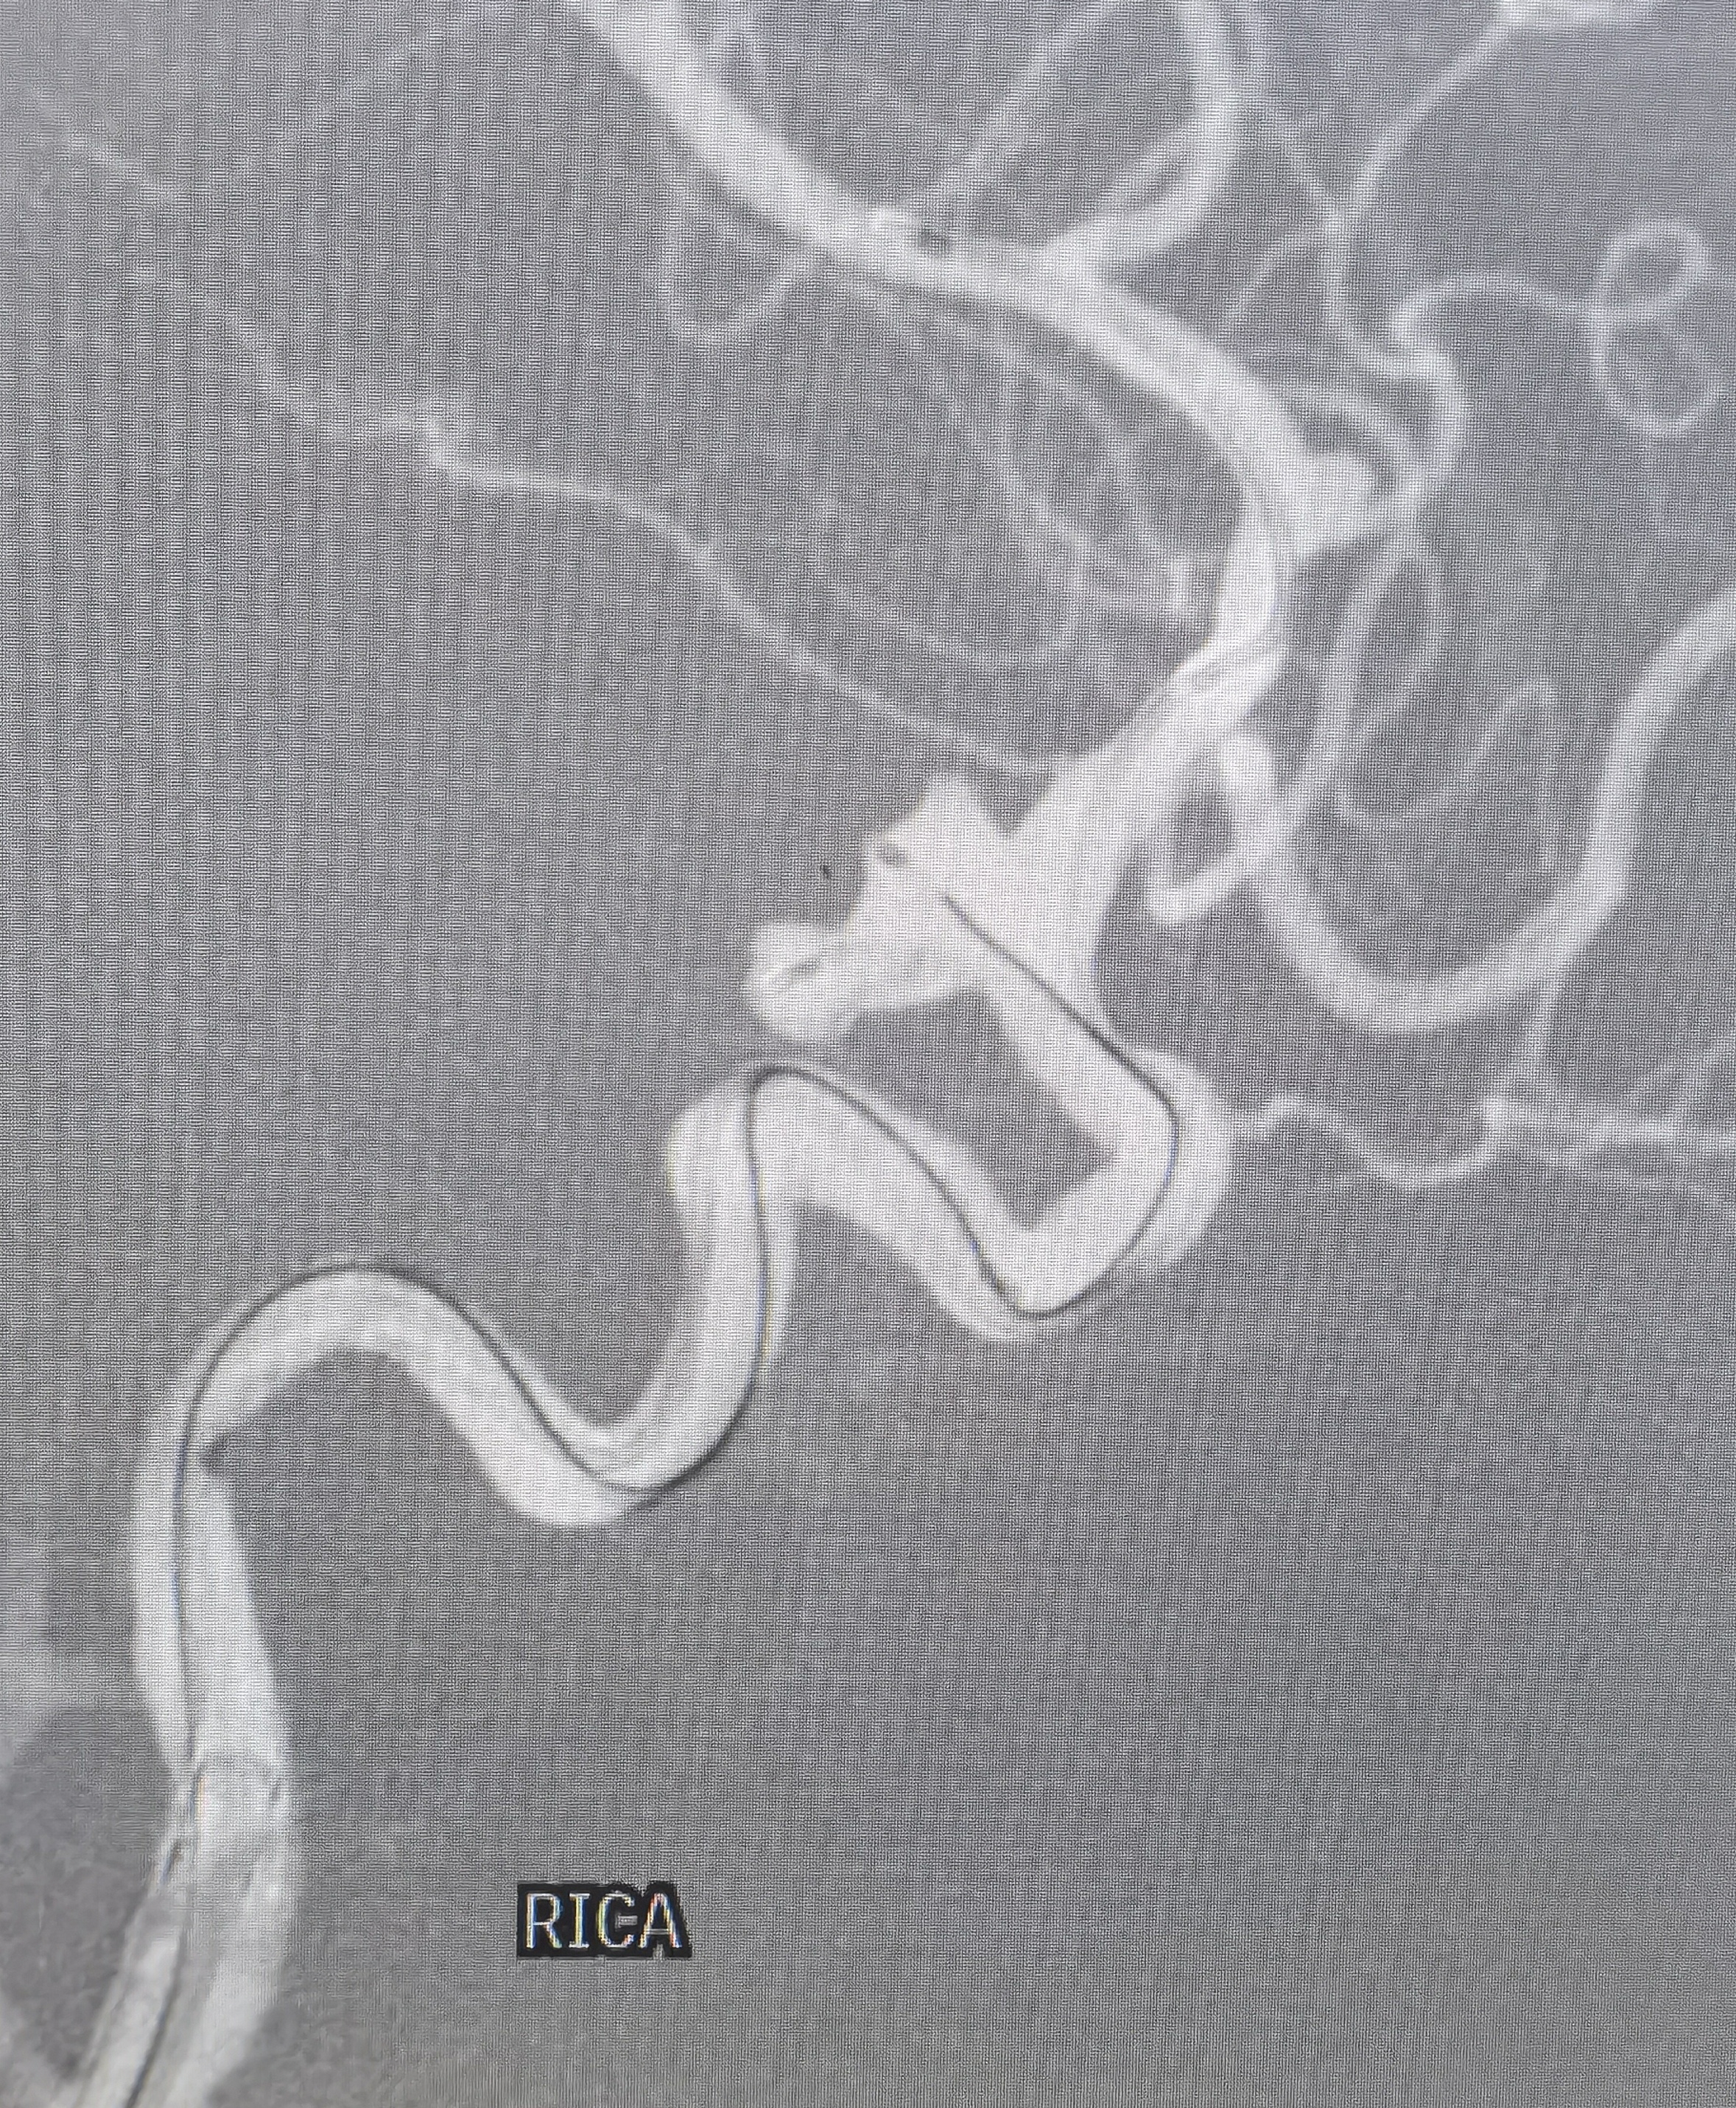

右侧颈内造影提示后交通不规则动脉瘤

椎动脉造影提示右侧P1良好,无需刻意保留后交通动脉

3D重建情况

拟支架辅助+双微管栓塞,微导管布局情况